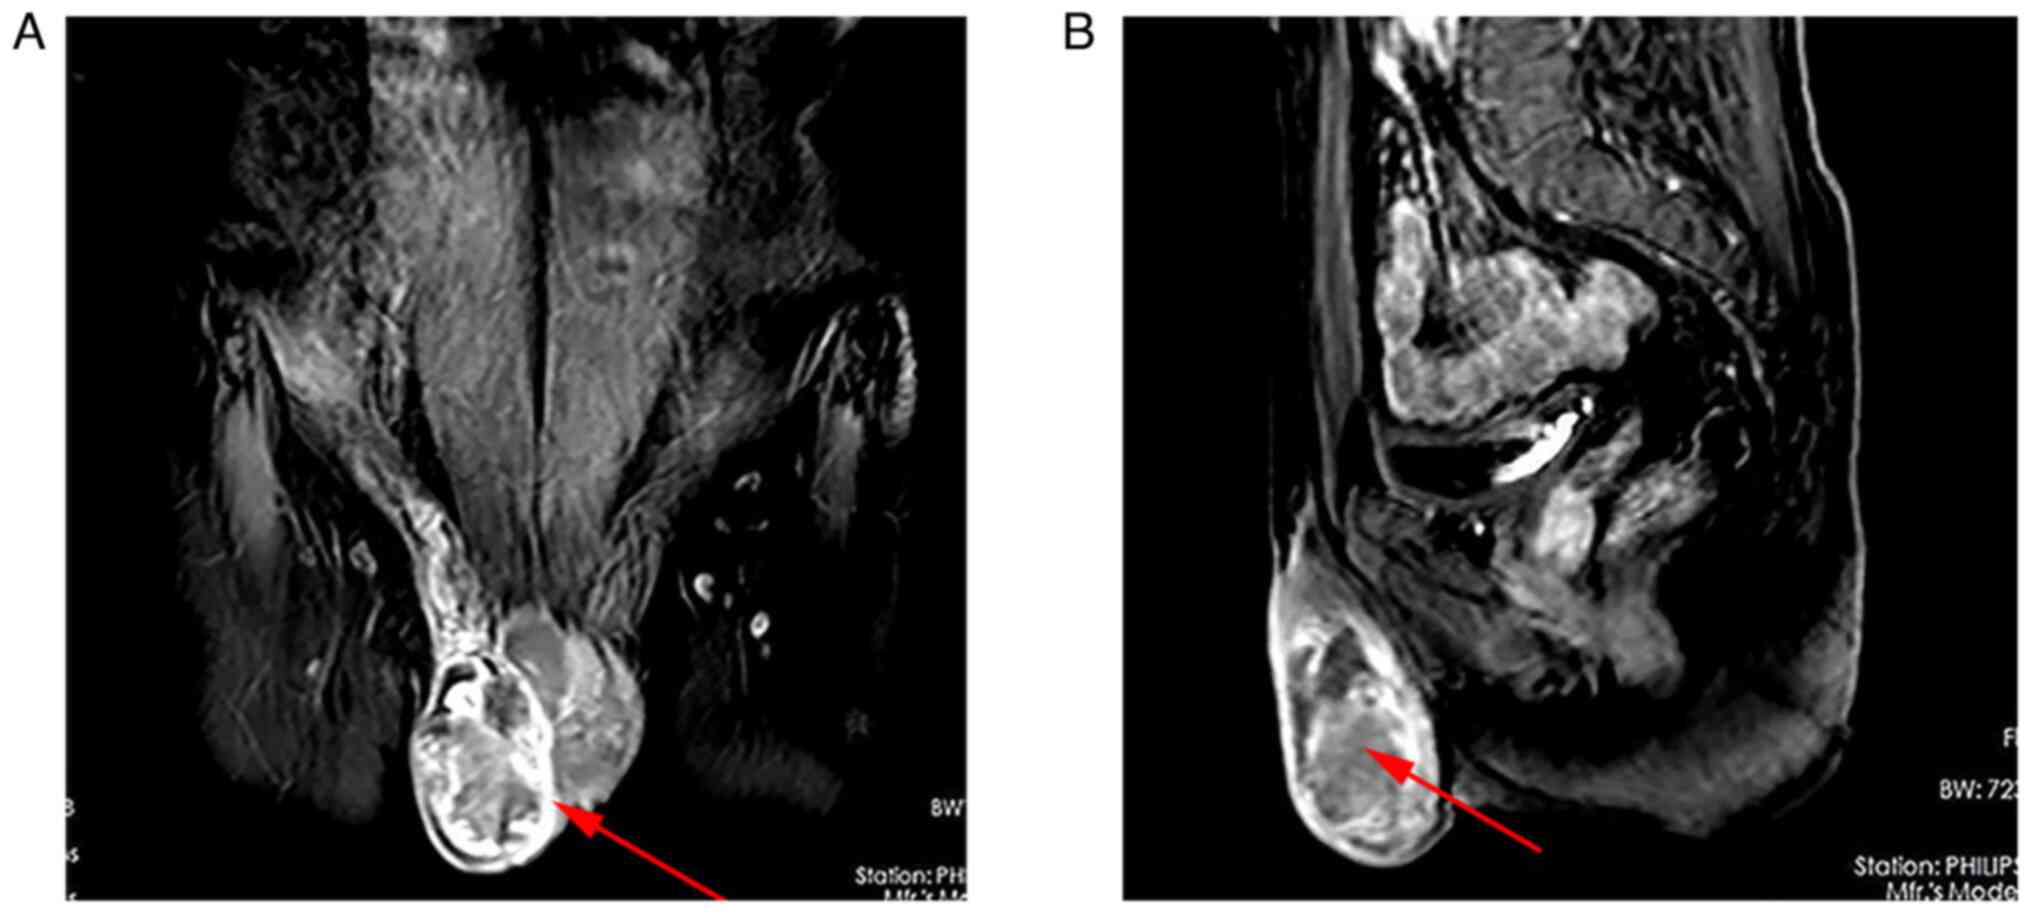

Magnetic resonance imaging (MRI) of the pelvis showed a right scrotal mass with malignant features (6x4.8x3.4 cm) (Fig. 1A and B). A computed tomography (CT) scan of the chest revealed multiple metastases to the bilateral lungs. A brain MRI was then performed for further evaluation and showed no malignant lesions in the brain.

Figure 1

(A) Coronal and (B) sagittal cuts of the pelvis show a swelling mass of the right testis with malignant features (red arrows).